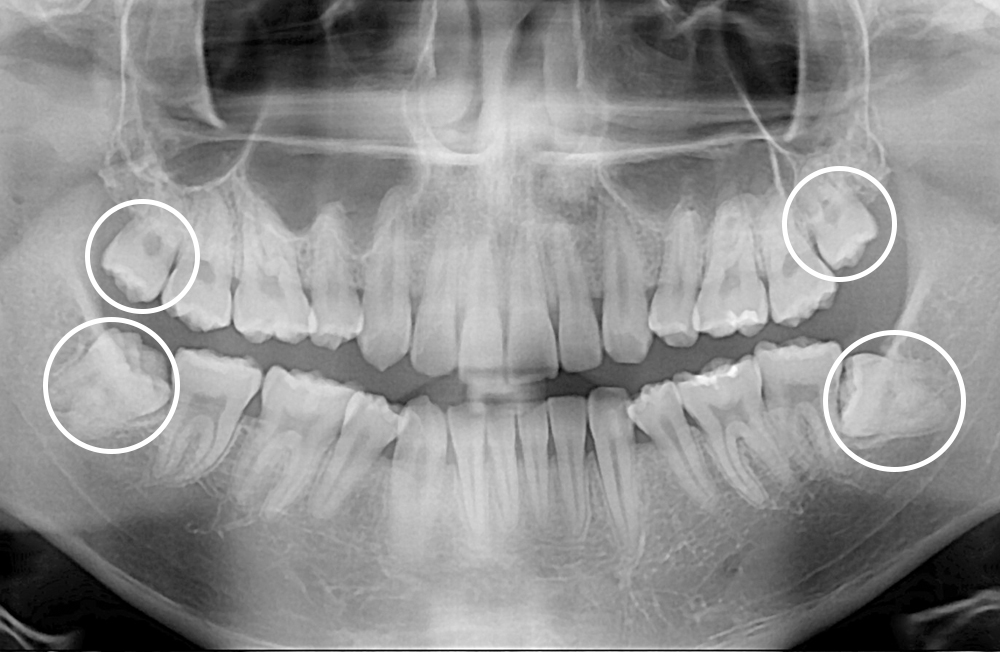

[사랑니] 매복 사랑니 발치

치료전 : 2020-10-13